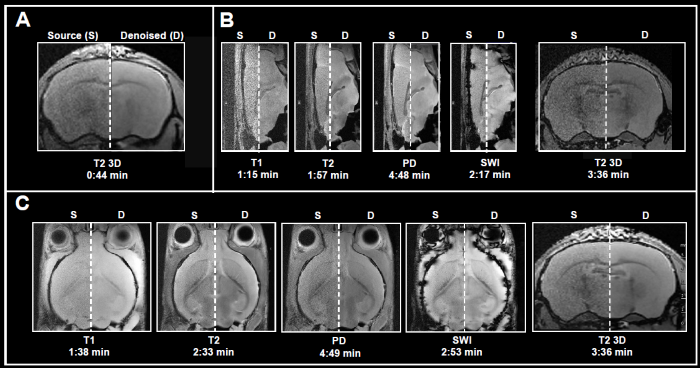

Fig. 4 displays examples of ex vivo brain scans of different contrasts and orientations gathered in less than 5 minutes. The data was obtained from 3, 7, and 9.4 Tesla tools. To achieve the desired short acquisition time, standard protocols prepared for each system were improved by removing averaging, as seen in Fig. 4A-C.

This resulted in 7-15 times faster acquisition times compared to the original protocols. Yet, given the chosen resolution, no averaging resulted in noisy images. Reconstructing the obtained data with the denoising algorithm successfully removed noise from images and delivered high-quality images.

Figure 4. Examples of fast brain scans. Ex vivo data of a fixed mouse head acquired with different image contrasts, geometries and orientations. Data were acquired at A) 3 Tesla, B) 7 Tesla, and C) 9.4 Tesla. Images were reconstructed with no denoising (Source) and with a network Strong and applying 50% pre-denoising and a denoising level of 70% (Denoised). Image Credit: Bruker BioSpin Group